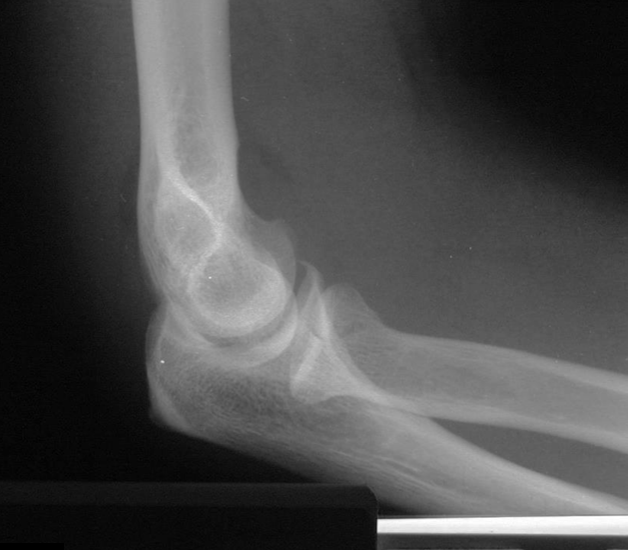

8

Q

What is the diagnosis?

What radiographic sign is present?

A

Intracapsular fracture with effusion/lipohemarthrosis

Sail sign present